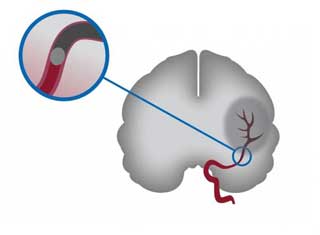

Процесс образования тромба происходит при повреждении стенки сосуда, что приводит к образованию сгустка крови. Это может происходить в различных местах, включая внешнюю оболочку мозга, а также артерии и вены, которые снабжают этот жизненно важный орган кровью. Данная ситуация может возникать как у взрослых, так и у детей.

Опасность, которую представляет тромб, заключается в его способности блокировать просвет сосуда. Это может привести к серьезным последствиям, вплоть до летального исхода.

Угроза исходит как от неподвижного тромба, так и от того, который может оторваться. В последнем случае риск закупорки сосуда значительно увеличивается. Ток крови может унести блуждающий тромб к любому органу, где он может перекрыть кровоток, что влечет за собой серьезные последствия.

Закупорка артерий головного мозга чаще всего возникает из-за образования бляшек.

Атеросклероз сонных артерий приводит к образованию тромба, состоящего из холестерина. Постоянное накопление бляшек на стенках сосудов вызывает сужение их просвета или полную блокировку.

Хрупкость таких тромбов приводит к тому, что от них отрываются эмболы — небольшие частицы, которые с кровотоком перемещаются по сосудам головного мозга. Это создает риск развития ишемического инсульта.